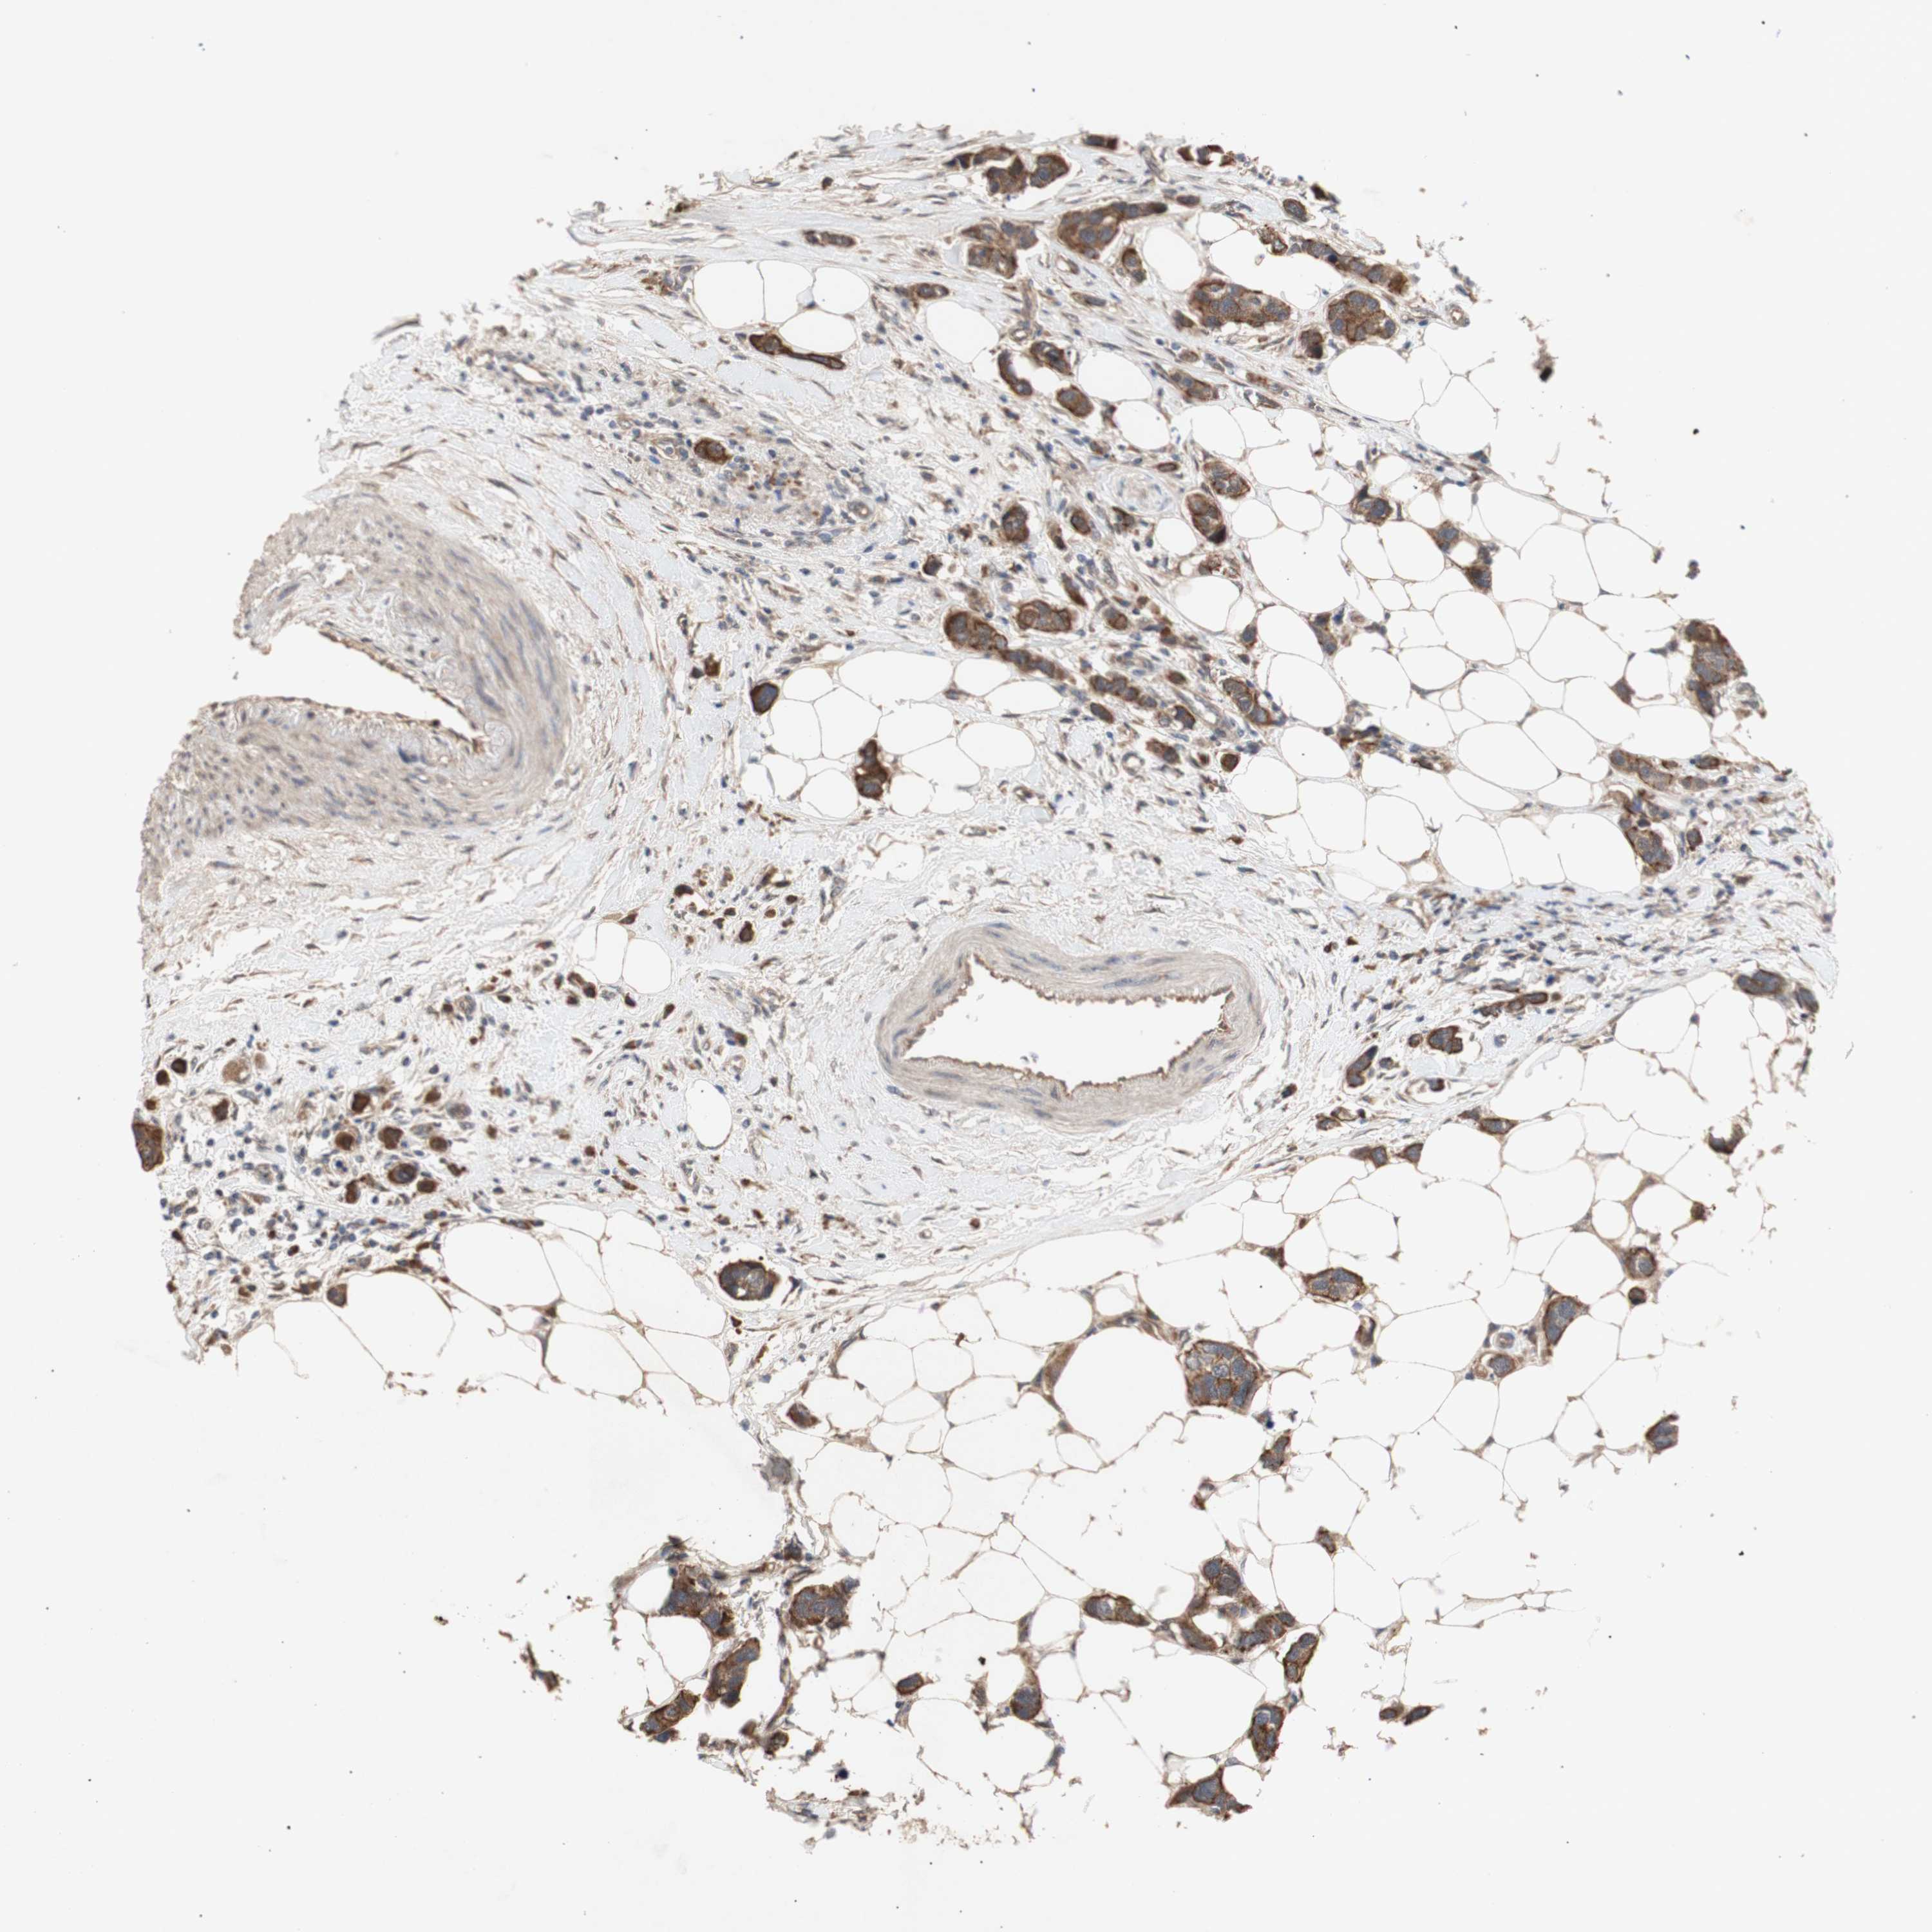

CANCER BREAST CANCER Show tissue menu

BRCA TCGA BRCA VALIDATION PROTEIN EXPRESSION

ANTIBODIES

AND

VALIDATION